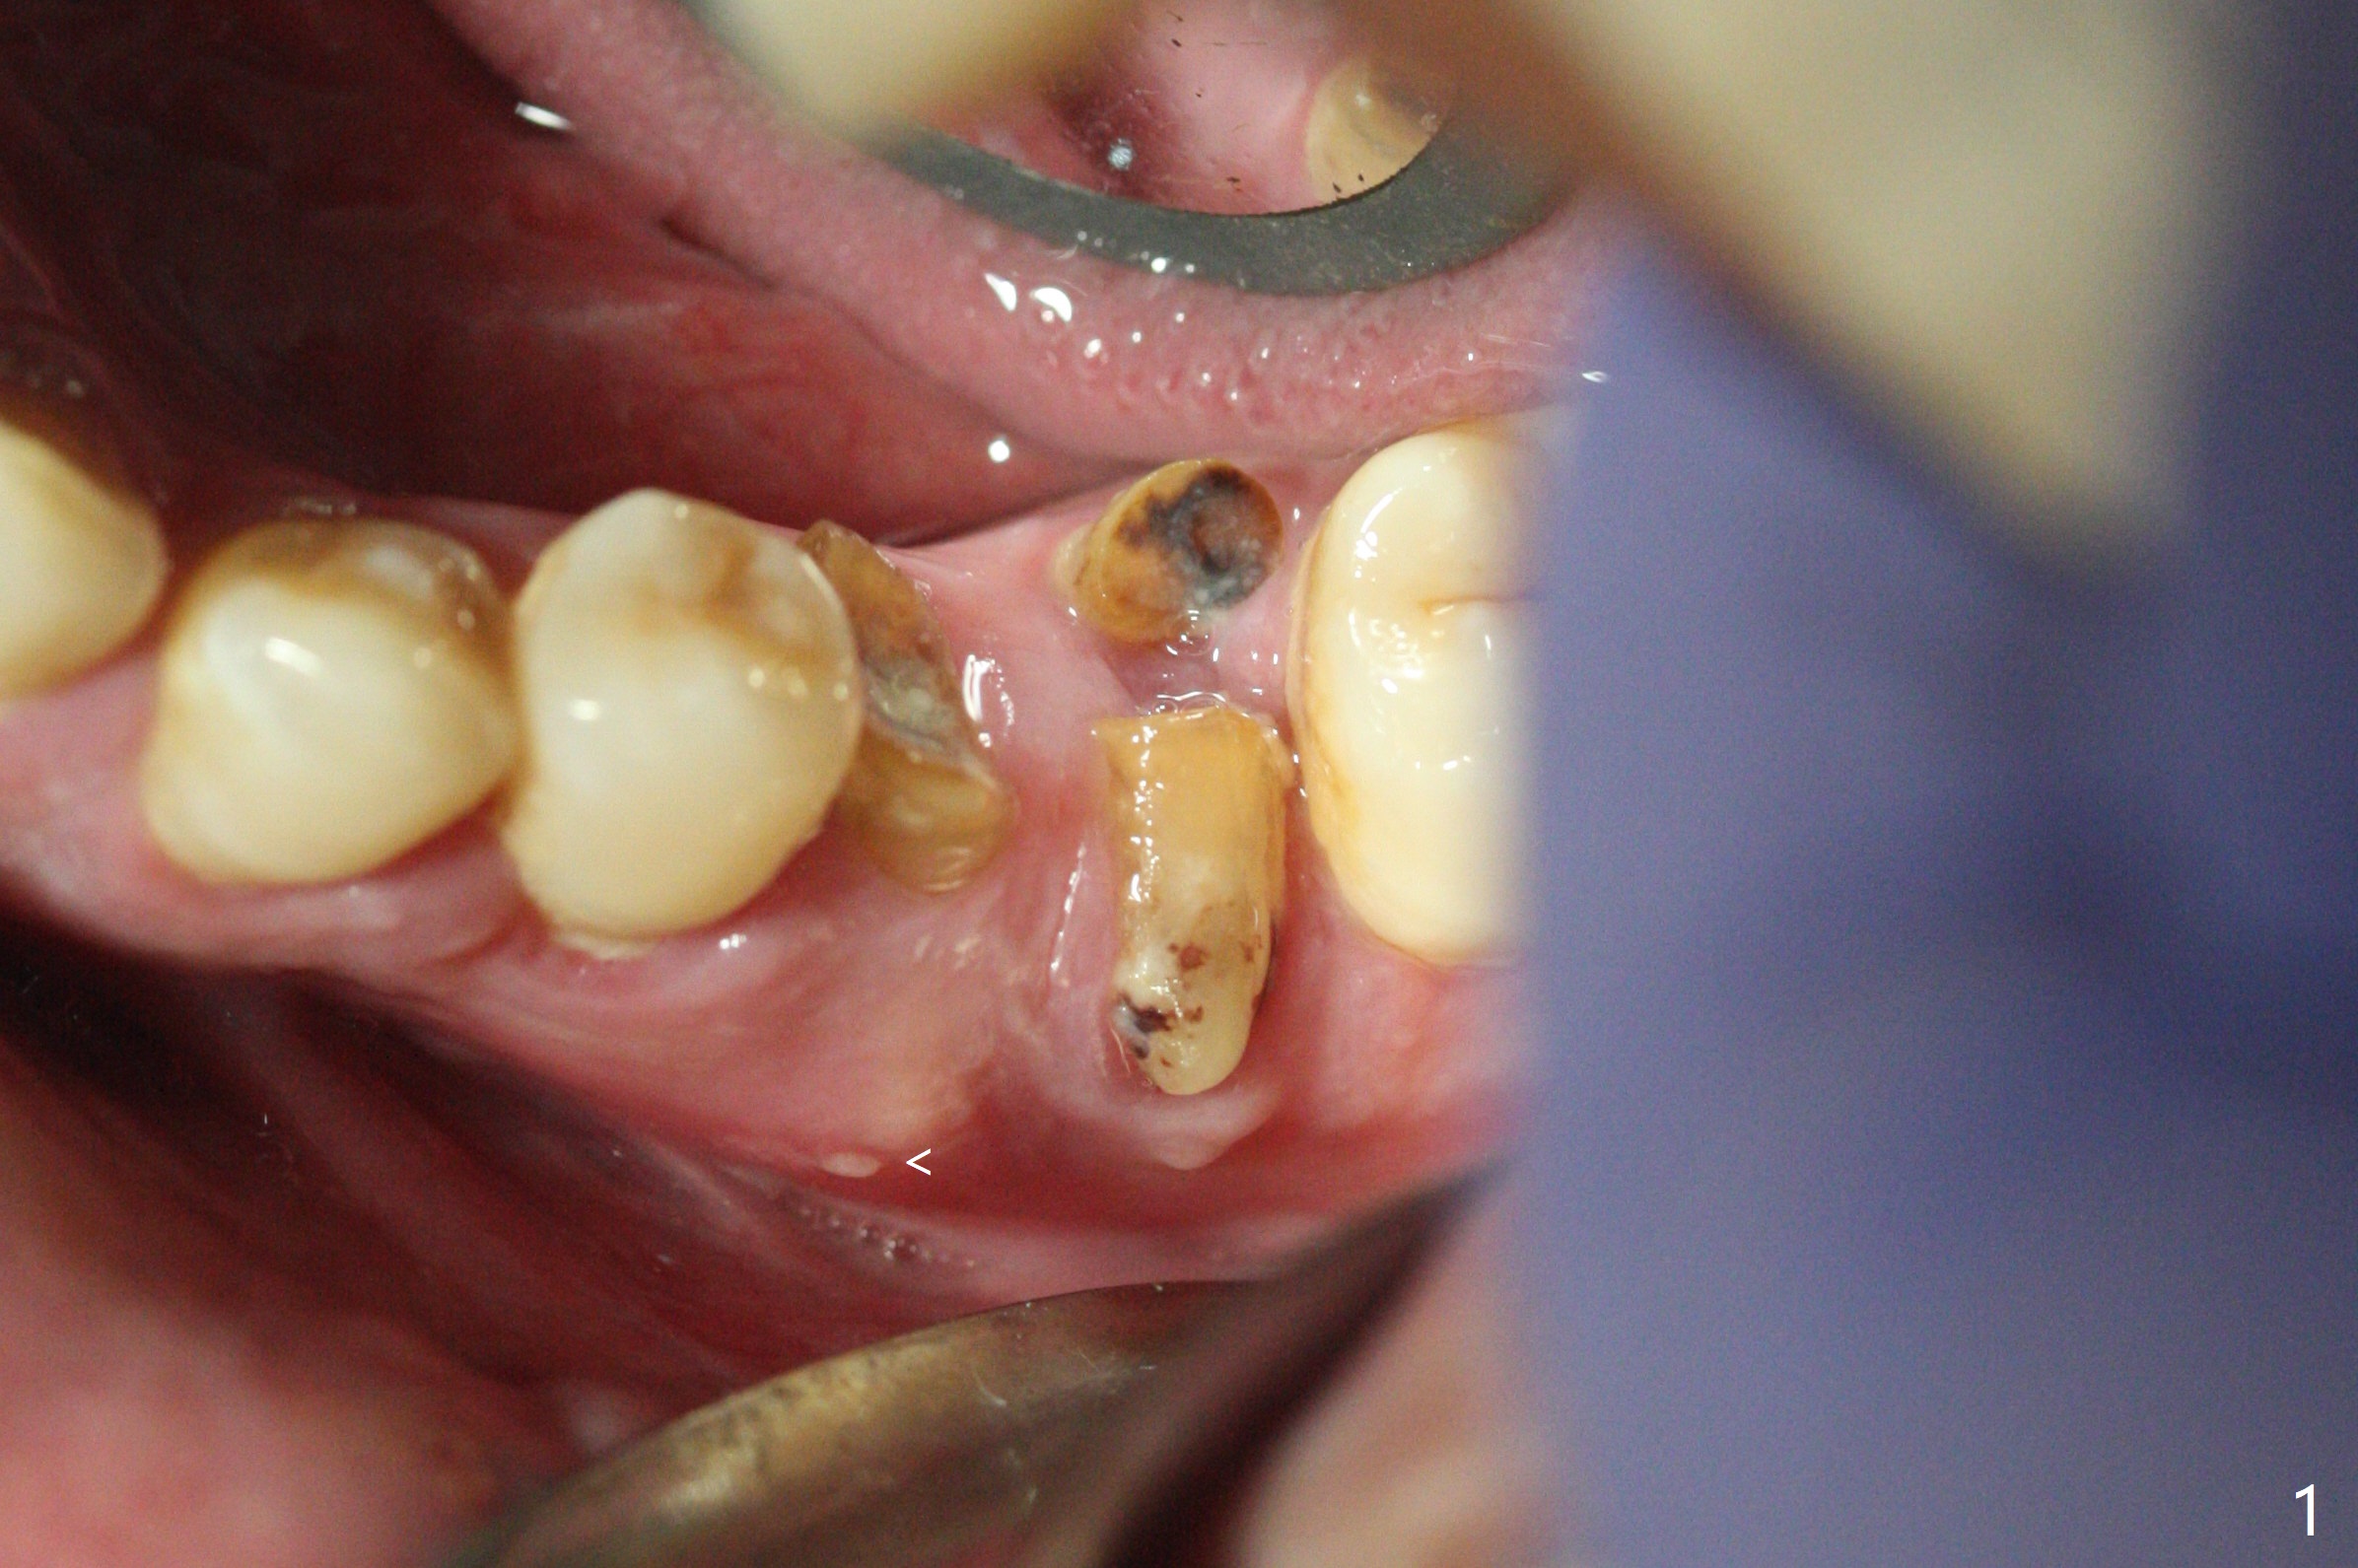

In spite of smoking reduction (1ppwk), the infection at #19, including buccal fistula (Fig.1 <) seems to be so severe that it affects pain threshold. Local anesthetics have to be added, including Bupivacaine IANB. When 4x10 mm drill is being applied, the patient feels pain. The plan is to use 4x11.5 mm drill as a final one. A 4x9 mm dummy implant is placed with 2.8 mm implant exposed (Fig.2 >), but it is subcrestal mesiodistally. Primary stability of a definitive 4.5x9 mm implant is satisfactory (Fig.3), but after initial bone graft, a 5x5.7(4) mm abutment is unable to be seated completely (<). Following 4.6 and 5.6 mm bone profile drills, the abutment remains incompletely seated (Fig.4). After fine turning, the abutment is fully seated; final round of bone graft (sticky bone) is placed mesiodistally (Fig.5 *) and buccolingually (Fig.6,7). It appears that there is tight fit between IBS implant and abutment. It is hoped that the excess bone graft with PRF is able to cover the coronal portion of the implant. If not, socket preservation should be done in this situation. In fact the implant is not placed lingual enough as compared to the design (Fig.6'). A 4.5 mm cortical drill should be used in a crown down fashion. In fact there is bone coverage coronally 5 months postop (Fig.8). Return to Prevent Molar Periimplantitis (Protocols, Table) No Deviation 12/14 Xin Wei, DDS, PhD, MS 1st edition 02/11/2020, last revision 06/30/2020